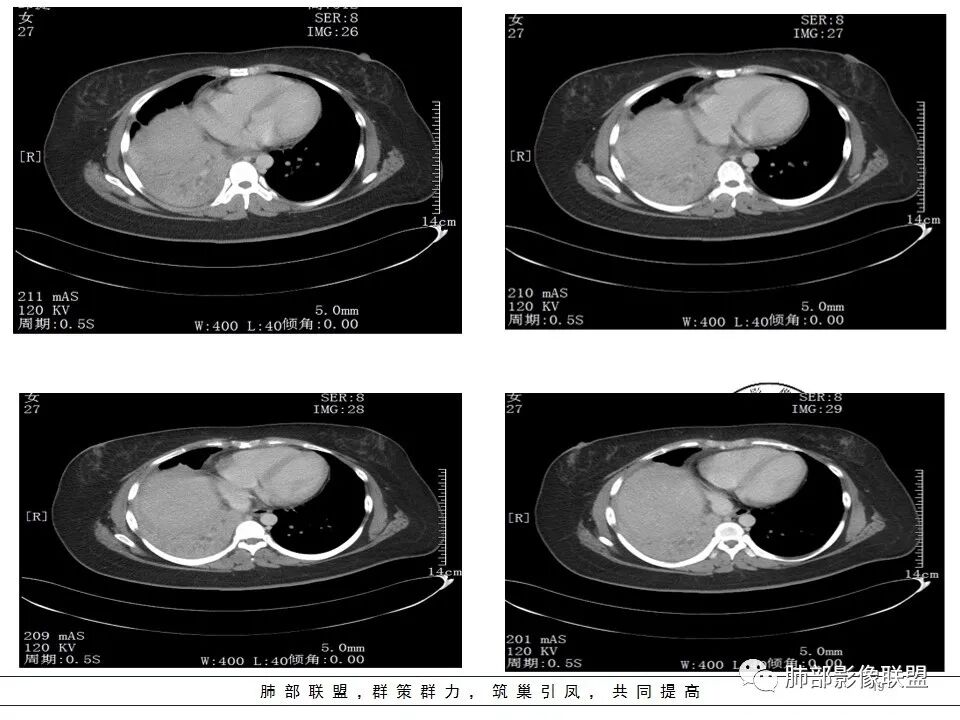

女,27岁,右肺下叶支气管闭塞,圆形软组织肿块和不张肺,增强不均匀强化,见片状坏死,多个纵隔淋巴结肿大,无钙化空洞及卫星灶;考虑恶性占位,肺肉瘤或鳞癌合并肺不张,鉴别诊断:结核,肺脓肿

发热咳嗽,右肺下叶可见团块状实变密度影,局部膨隆,并可见胸膜牵拉,相应下叶支气管未见显示,增强后肿块近端呈不均匀强化,可见大片状坏死,内血管略变细,毛糙,周围肺组织支气管内可见粘液栓形成,另纵膈肿大淋巴结,考虑恶性肿瘤,鳞癌,伴阻塞性肺不张,淋巴结转移

CT扫描示右肺下叶支气管堵塞,类圆形大肿块伴胸膜下大片肺实变影,增强扫描类圆形肿块延迟强化,见少量坏死,余实变区增强可见内部血管走行。纵隔见肿大淋巴结。考虑为恶性病变伴右肺下叶肺不张

右下肺门不规则结节强化,并远端支气管粘液栓及大片实变,实变边缘叶间裂膨隆,考虑支气管占位并阻塞性肺炎,涎腺类恶性肿瘤(粘液表)需要鉴别。

右中间支气管阻塞,右肺下叶实变,未见明显支气管空气征,增强中间支气管内病变未见明显强化,纵隔淋巴结增大,偏向恶性病变,结合病史,青年人,肿瘤性病变,支气管表皮样粘液癌可能。

年轻女性,右肺下叶支气管堵塞伴不张,增强轻度强化,血管走形自然,右肺门区见强化结节影,支气管来源肿瘤伴不张。不张软组织影跨右肺中叶及下叶,需鉴别纤维瘤。

右下肺大片实变影,近肺门处明显膨隆,远端可见粘液栓形成。纵隔多发肿大淋巴结。增强扫描可见血管造影征,血管边缘欠光整。考虑肿瘤。

患者青年女性,发热6 天,咳嗽、咳痰3天。为黄脓痰。胸部CT:右肺体积稍小,右中间支气管肿物堵塞,中叶、下叶大片实变不张,与正常肺组织分界清楚。增强实变影明显强化,右下肺支气管近心端见类圆形强化结节影,血管纤细,部分支气管显影变细,纵隔淋巴结肿大。结合无呼吸困难症状,病程长。综合考虑低度恶性病变并阻塞性肺炎,类癌可能大,鉴别结核、淋巴瘤。

右肺中下叶实变伴气管腔内粘液栓形成,肺门区见不规则软组织肿块,气管腔狭窄,截断,呈中等强化,纵膈内肿大淋巴结,考虑气管腔内原发肿瘤性病变伴肺实变

右肺体积缩小,右肺巨大低密度肿块并下叶不张,无胸膜尾征,定位肺内,右中间支气管堵塞,肿块内可见粘液栓,不均匀强化,其内血管走行自然,右下肺受侵边缘不整,纵隔内淋巴结肿大,考虑为恶性,年轻女性,粘液表皮样癌首选,其次肉瘤或类癌。

纵隔淋巴结肿大,以2/4R区、3区为主

这里不知道是不是内乳的淋巴结?

如果是内乳淋巴结,代表淋巴瘤

纵隔淋巴结大

常规支气管腔内肿瘤,淋巴结转移,恶性吧

这么年轻——粘液表皮样癌?类癌?

本病例特点是中叶病灶和下叶病灶不一样,支气管腔内的病灶又是怎么样的呢?我们要是有沿支气管重建的冠状位、矢状位会更有利于分析。第一,中叶病灶明显粘液样改变、低密度,且低密度区有占位效应、膨隆,确实要考虑粘液表皮样癌。第二,中叶和下叶支气管显示不出来,但血管显示出来了。中叶病灶血管稀疏、细小,下叶病灶血管粗大、走形正常。朝外肺不张实变,不是单纯的肺不张,肺不张一般体积明显缩小、血管聚拢,该病例肿瘤于其中成分不一样,所以上叶部分病灶考虑为下叶病灶占位效应及膈面向上推压引起,中叶萎缩。综合腔内堵塞、纵隔淋巴结肿大要考虑恶性。

2.右肺中下叶大片实性密度影,体积有缩小,密度不均,不均匀强化,前份可疑小范围液性密度区。

3.中间段支气管阻塞,腔内隐约见息肉样结节或突入,结节有较明显强化,这很重要,说明它有生命力,强烈提示新生物,而非分泌物或异物等等。

4.年轻、女性,支气管腔内相关新生物,会想到类癌或涎腺类肿瘤,如粘液表皮样癌等。强化较明显类癌可能性较大。支气管鳞癌和间叶组织肿瘤的可能性都非常小。